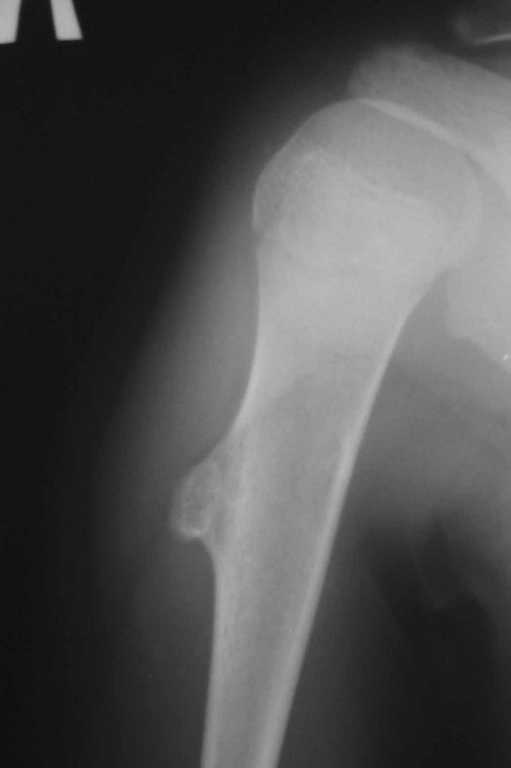

Уважаемый Антон. У ребенка типичный костно-хрящевой экзостоз в области проксимальной трети плечевой кости. Удаление экзостоза, уровень резекции по проекции интактной кортикальной пластинки. Костная пластика не требуется

Согласен с Ihor и Игорем Владимировичем - имеет место костно-хрящевой экзостоз. Необходима резекция в пределах здоровой кости без костной пластики

Обычная Solitary Osteochondroma или экзостоз относится к часто встречающимся доброкачественним опухолям. При давлении на нерв или на сосуды могут быть характерные симптомы, а так клинически не проявляется и обнаруживается случайно при исследованиях по другим поводам.

Обычная простая плоскостная резекция решит все